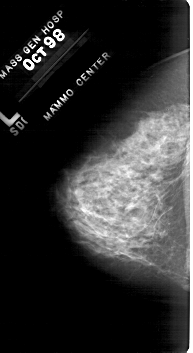

A_1819_1.LEFT_CC

LEFT_CC LINES 5281 PIXELS_PER_LINE 2881 BITS_PER_PIXEL 12 RESOLUTION 43.5 NON_OVERLAY

FILE: A_1819_1.RIGHT_CC.OVERLAY

TOTAL_ABNORMALITIES 2

ABNORMALITY 1

LESION_TYPE CALCIFICATION TYPE PLEOMORPHIC DISTRIBUTION CLUSTERED

ASSESSMENT 4

SUBTLETY 4

PATHOLOGY MALIGNANT

ABNORMALITY 2

SUBTLETY 2